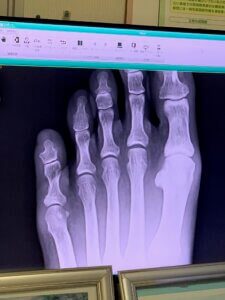

足の小指骨折!!

生れてはじめて骨折しました…

朝、水の段ボールの角にぶつけ、痛い!!と思ったものの

あっさり「骨折してますね」。

完治までは1か月半から2か月と。